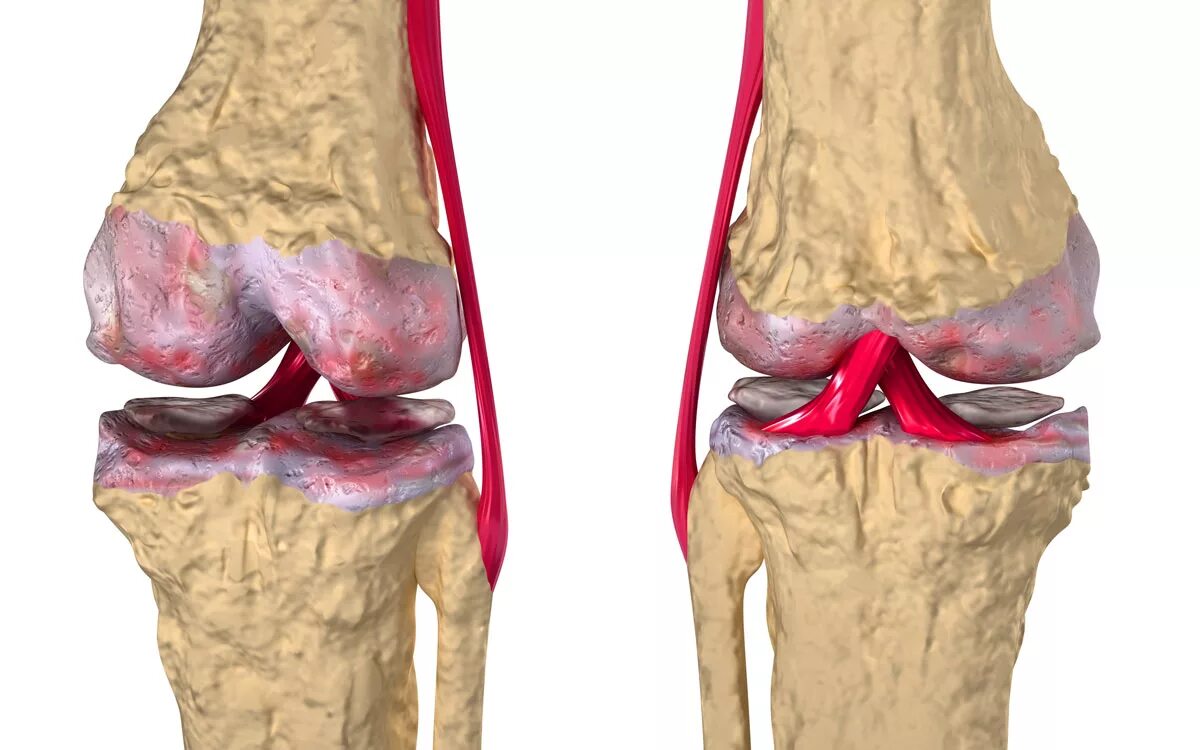

Гонартроз коленного сустава какой врач